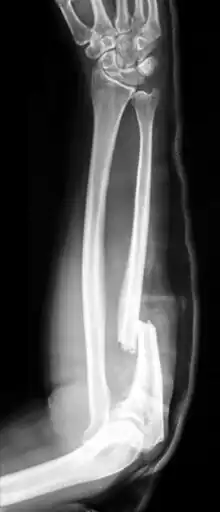

| X-ray of Monteggia fracture of right forearm | |

The Monteggia fracture is a fracture of the proximal third of the ulna with dislocation of the proximal head of the radius. It is named after Giovanni Battista Monteggia.[1][2]